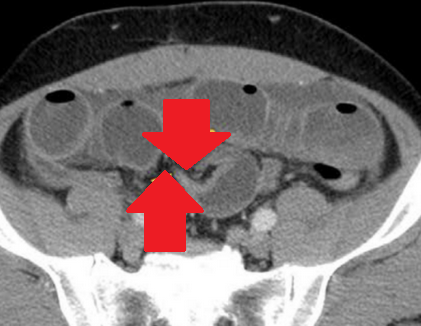

Red arrows — transition point. Multiple air-fluid levels (Courtesy Dr. V. Penopoulos)